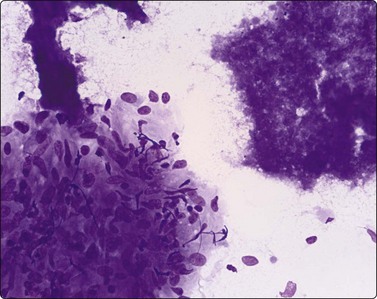

Skin nodules and palpable subcutaneous lesions are easily sampled by FNB. Pyogenic abscesses and infections such as tuberculosis9 are easily differentiated from tumor metastases, and, in the HIV population, from Kaposi’s sarcoma. Both superficial and deep fungal infections can be diagnosed by FNB and, especially in the IC, may represent disseminated fungal infection due to Aspergillus spp, Cryptococcus neoformans, histoplasmosis, blastomycosis,10 sporotrichosis and Candida spp,11 or one of the increasing number of other reported fungal infections producing subcutaneous nodules or mycetomas, including, Phialophera parasiticus, Sporothrix schenkii, Cladosporium spp, Exophiala jeanselmei12 and Microsporum canis.13 Actinomyces producing actinomycetomas, and rhinosporidiosis,14 filariasis,15 myaisis,16 leishmaniasis and leptosporosis all occur in the skin. The tuberculoid, borderline and lepromatous variants of leprosy, as well as neuritic and cystic lesions, can all be diagnosed.17 FNB of cellulitic skin to diagnose surgical wound skin infections18 and Buruli ulcers19 by direct smears and culture have been recommended. Skin nodules due to myaisis are rare but eminent FNB targets (Fig. 18.1).

image

Fig. 18.1 Cutaneous myaisis

Dipteran larva in background of pus from 23-gauge FNB of skin abscess (HE, ×600).

(Courtesy Dr Peter Pogany, Budapest, Hungary)